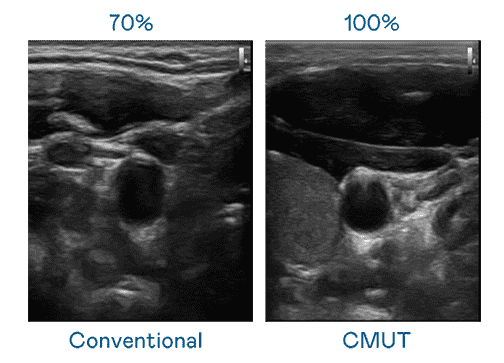

CMUT 技术是一种用电容式微机电元件来产生超音波讯号的技术。。与传统 PZT 压电式技术相比,,,CMUT 频宽增加 30%,,,,更宽频的超音波讯号让影像解析度大幅提升,,,是实现高影像品质医疗超音波扫描、、、促进精准医疗发展的关键技术。。

大频宽带来超清晰影像

超音波影像的解析度高低,,,,首先取决于探头能发出的讯号频宽。。。冰球突破 CMUT 可提供高清晰的超音波讯号,,提供高频宽、、、高灵敏度、、、、影像纹理细节更高的超音波影像,,,,协助医护人员缩短影像判读时间及利用精准的医疗影像进行诊断。。。